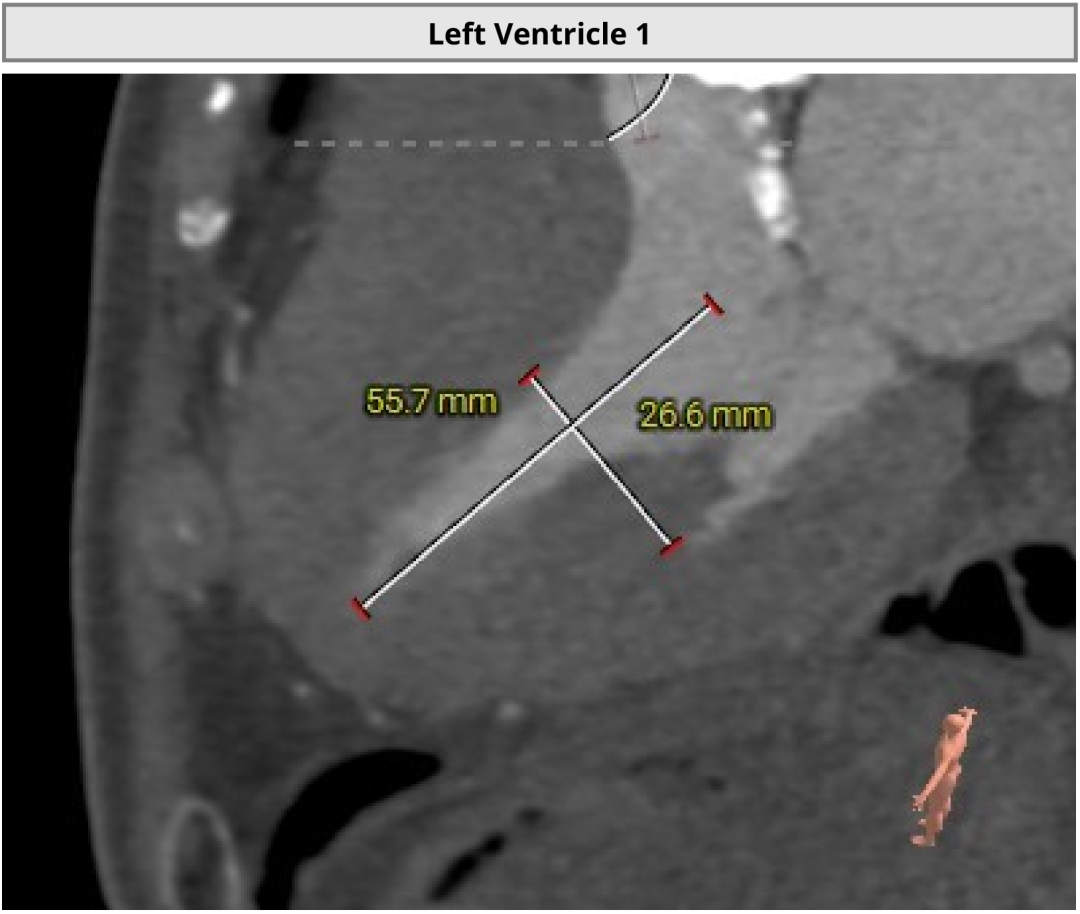

近日,昆山市中医医院心内科团队又成功为一名82岁高龄患者实施经导管主动脉瓣置换术。该患者主动脉瓣口面积仅0.2cm²,而正常成人主动脉瓣口面积一般约为3至4cm²。与此同时,患者还合并重度钙化的二叶式主动脉瓣、轻中度反流,左心室腔径偏小,并有帕金森病病史。多重高危因素叠加,意味着术中导丝跨瓣难度大,循环波动耐受差,整体风险很高。

进一步评估显示,患者瓣膜狭窄程度重,瓣叶钙化明显,左心室腔径偏小,手术中对器械通过、瓣膜释放以及循环稳定性的要求都更高。团队结合术前影像和整体身体状况,制定了周密的介入治疗方案,并做好相关风险预案。

CT评估

瓣膜评估